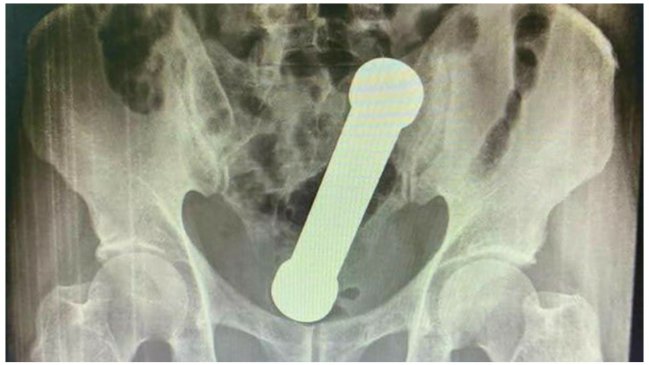

Sin embargo, las radiografías abdominales revelaron que el hombre tenía una mancuerna de 20 centímetros atorada a la altura donde el colon se conecta con el recto.

Posteriormente, el sujeto confesó que dos días antes se había introducido el objeto metálico de dos kilos sin lograr sacarlo después de su interior.